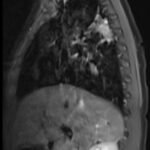

Pediatric neuroblastoma is famously characterized by an abdominal mass in a toddler with “raccoon eyes,” Horner syndrome, and/or opsoclonus myoclonus. However, rare cases may present with non-discrete symptoms and signs which create challenges for timely diagnosis. This case depicts a toddler with bulbar symptoms, including bilateral ptosis, dysphagia, drooling, head tilt and ataxia in a post-viral course mimicking other neurologic diagnoses, including myasthenia gravis. Magnetic resonance imaging (MRI) of the brain and spine uncovered a right adrenal mass along with heterogenous enhancement in multiple vertebral bodies and the clivus, consistent with metastatic disease. A diagnosis of neuroblastoma was confirmed with elevated homovanillic acid (HMA) and vanillylmandelic acid (VMA) levels and adrenal biopsy. The patient was treated with plasmapheresis for suspected paraneoplastic neurological syndrome and subsequent chemotherapy. In this case presentation, we review neurologic syndromes causing acute-onset pediatric bulbar weakness along with the patient’s key MRI findings.